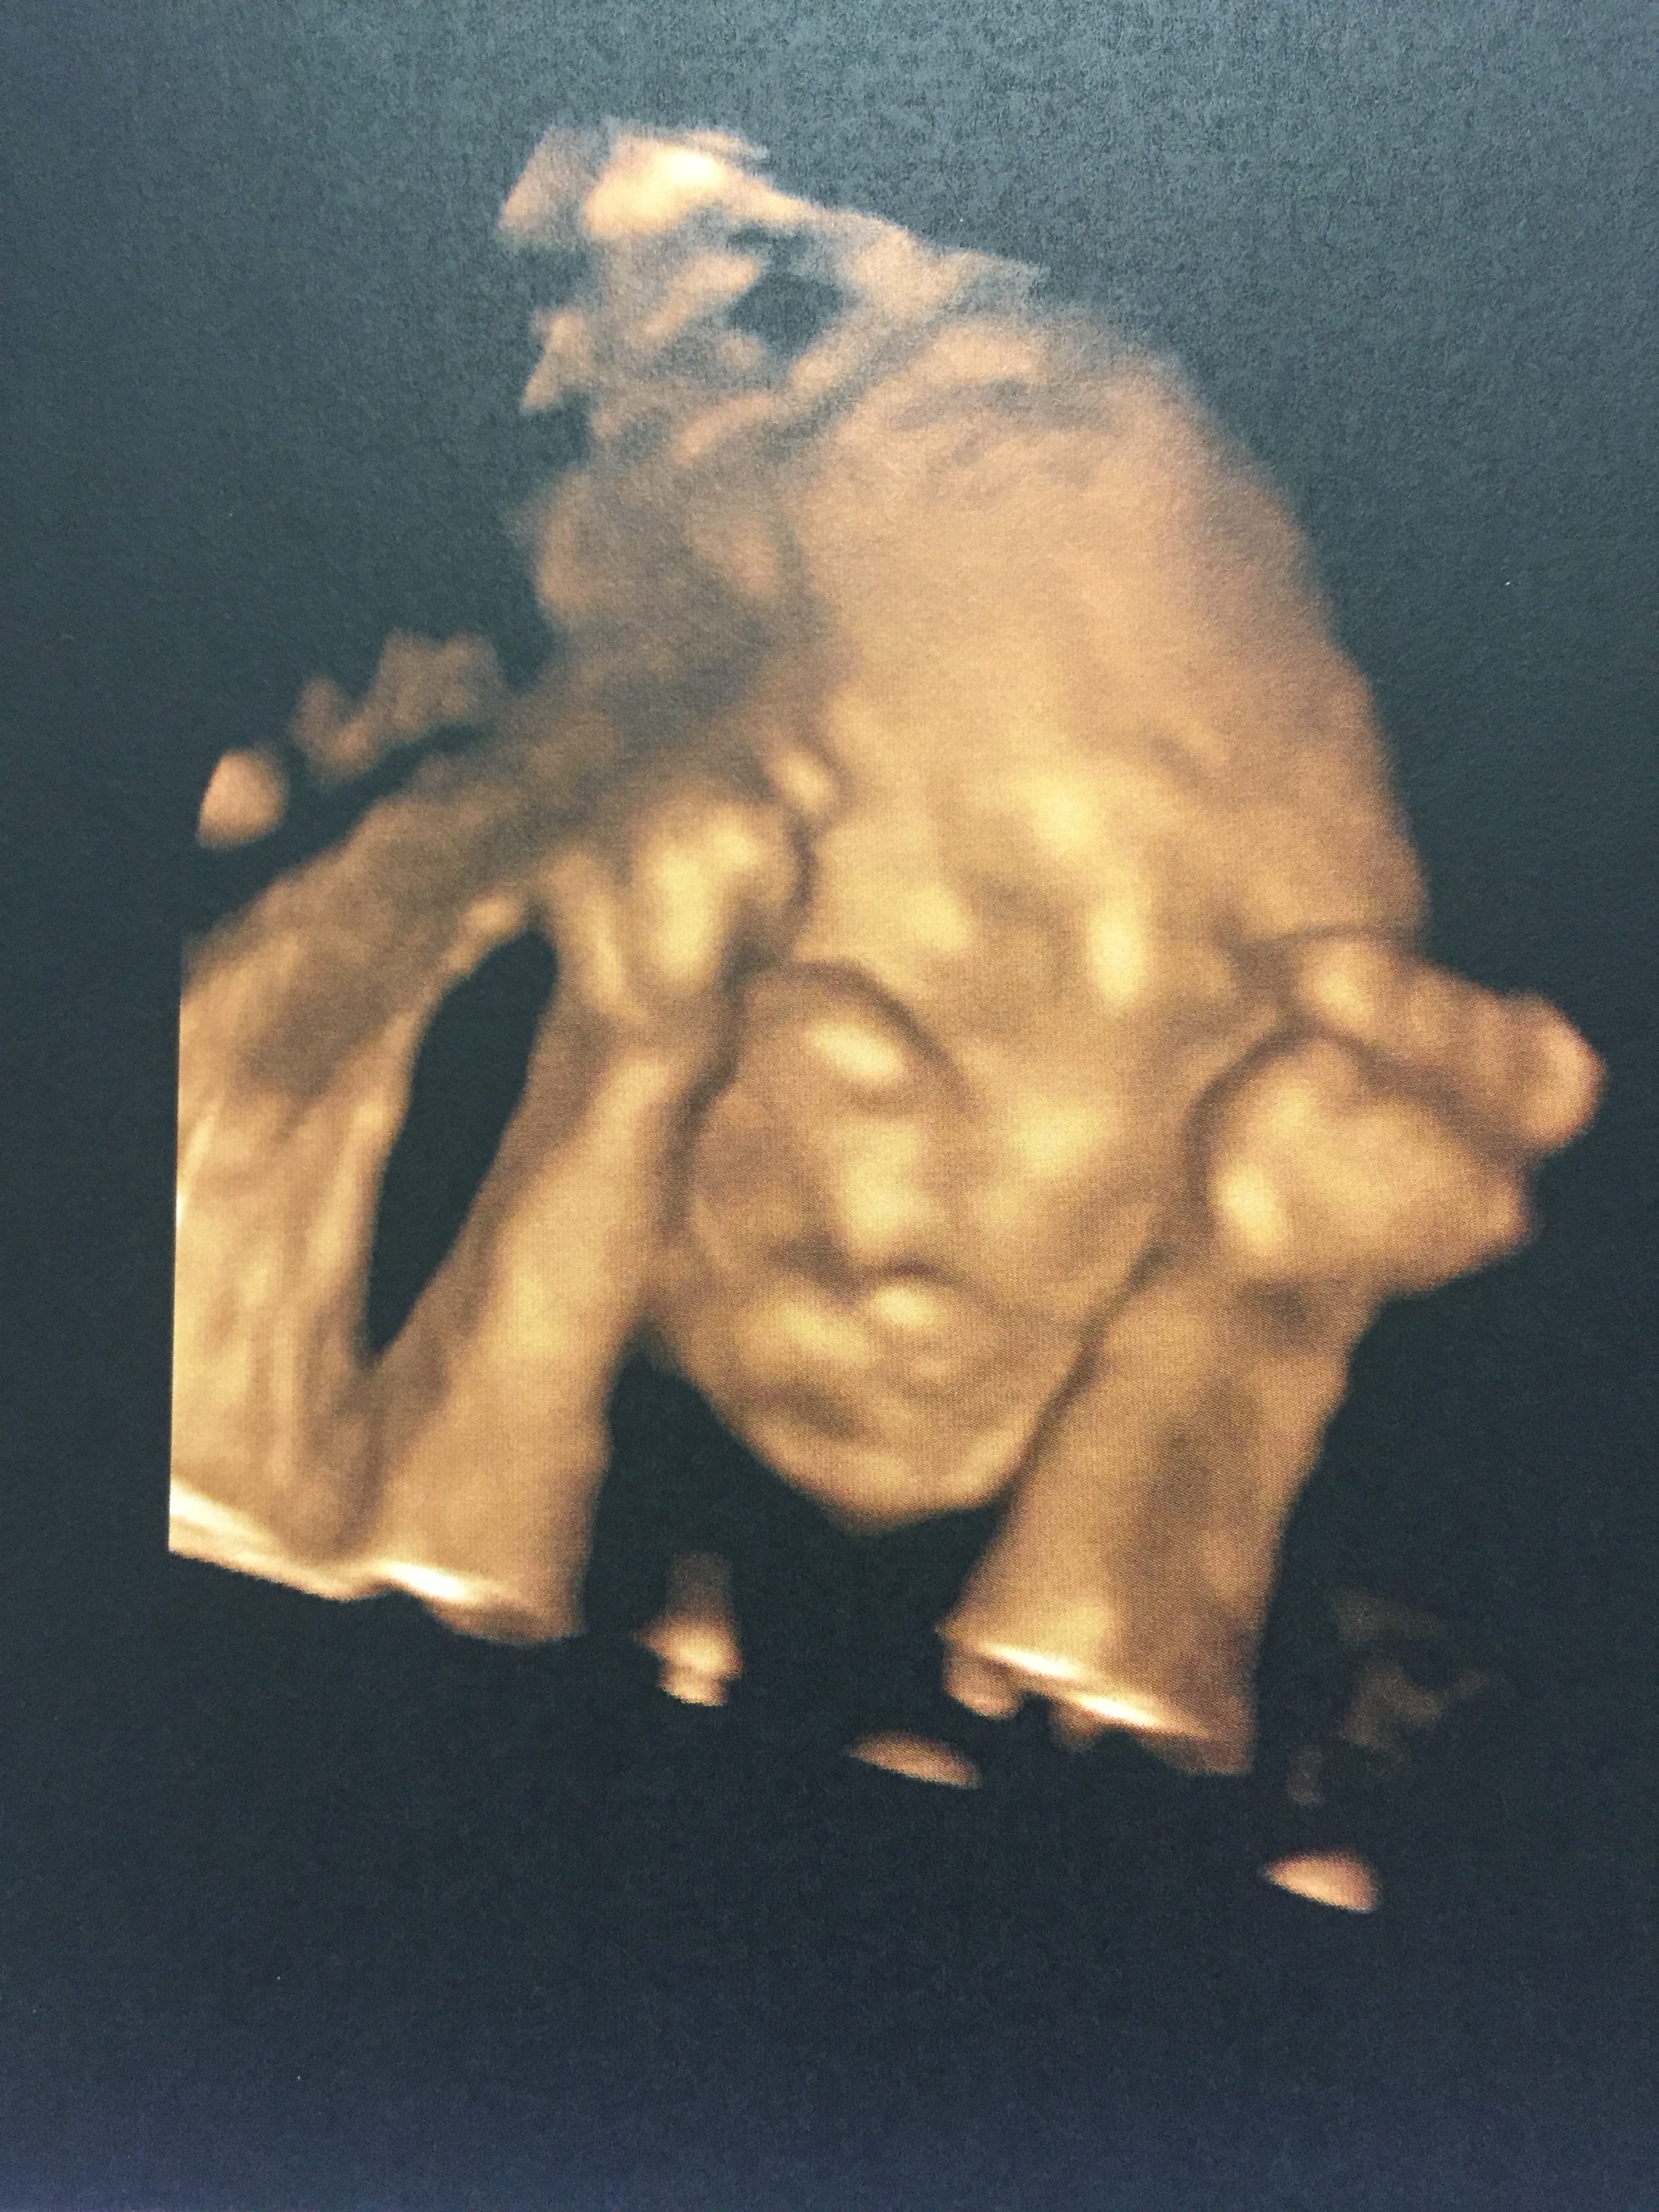

A Laura faz hoje dois anos e eu lembro-me de cada instante que passei desde o momento em que entrei nas urgências do Hospital dos Lusíadas até ao derradeiro momento em que a puxei literalmente para o meu peito. Recordo-me da espera, das contracções, da minha teimosia e resistência para que não fizessem nada que fugisse ao meu controlo. Lembro-me igualmente da adrenalina que foi percorrer o corredor até à sala de partos e eu e ela dentro da nossa bolha a preparar aquele momento. Lembro-me que só vacilei perante o som agudo dos materiais a bater uns nos outros enquanto o meu obstetra montava todo o arsenal. Pensei, por uma fracção de segundos, e se eu não for capaz de fazer isto? Mas rapidamente mudei a minha atenção, pedi para baixaram as luzes, colocaram música e as contracções marcavam o ritmo de tudo.